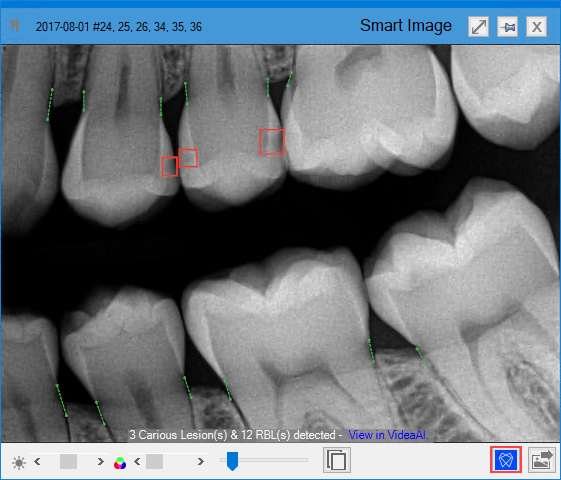

The Diagnostic Viewer appears, the image processes, and any caries Dentrix Detect AI found are outlined in red.

3. To view the details of the analysis or to hide the results, click the VideaHealth AI button.